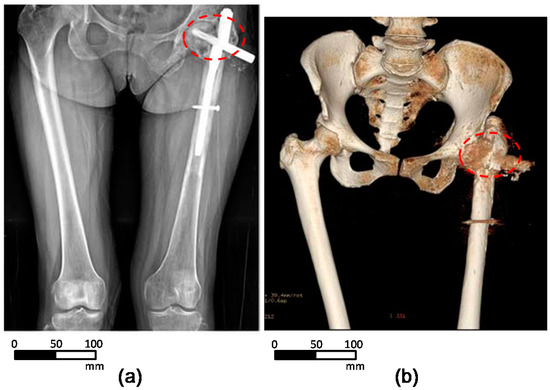

2.1. Patient Information

2.2. 3D-Reconstruction of the Pelvic Implant Model